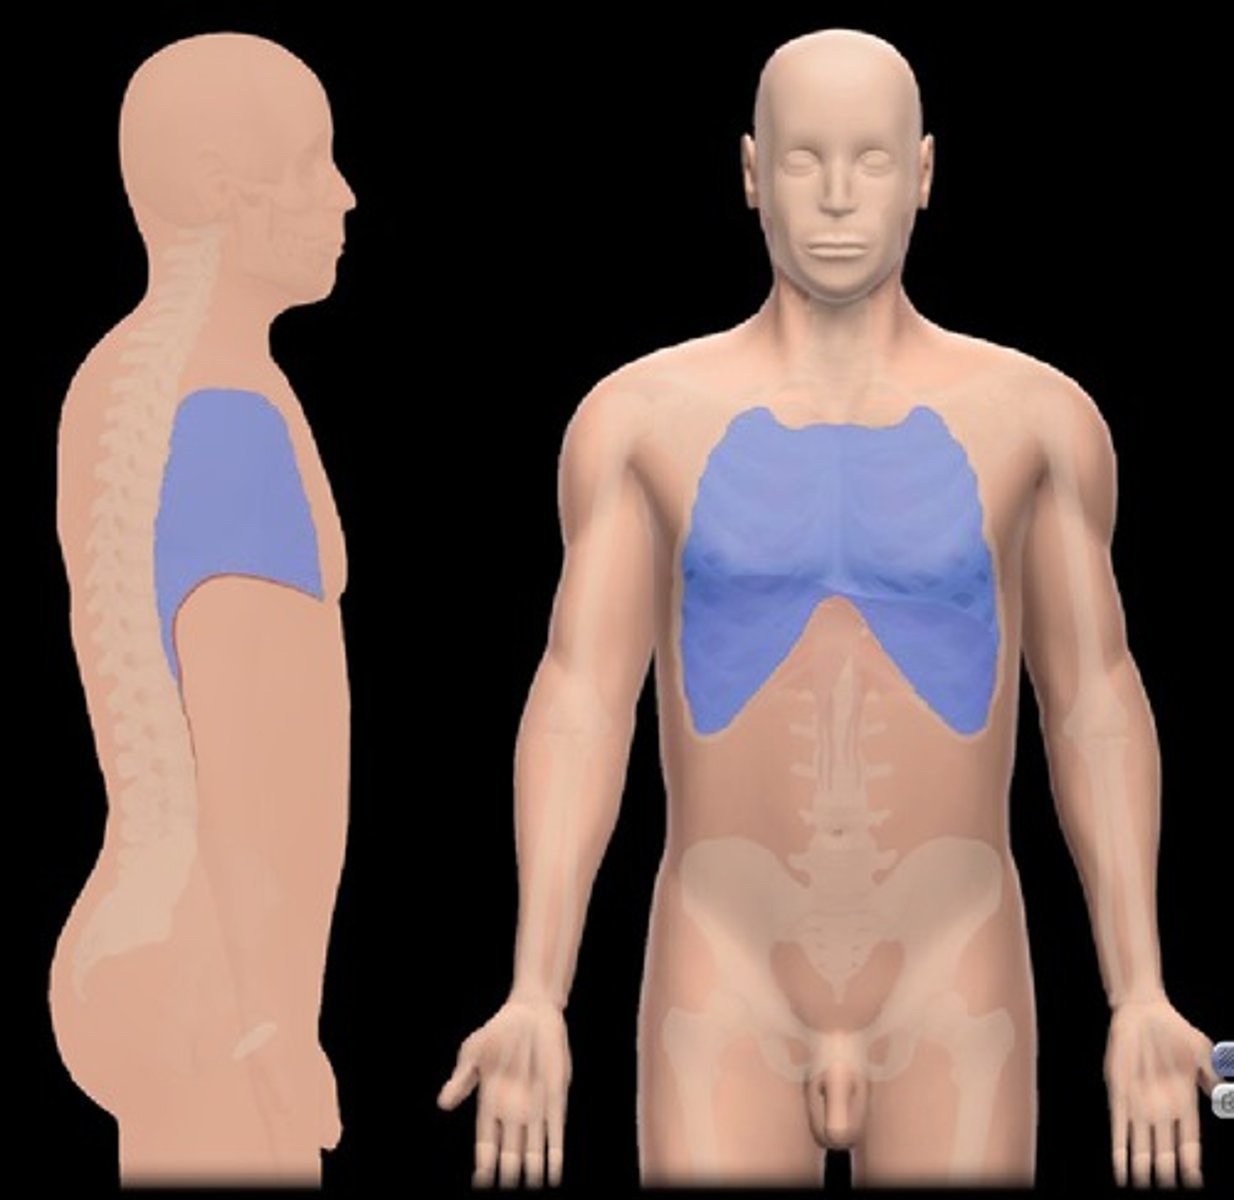

Thoracic

Chest

Vertebral

Area of the spinal column